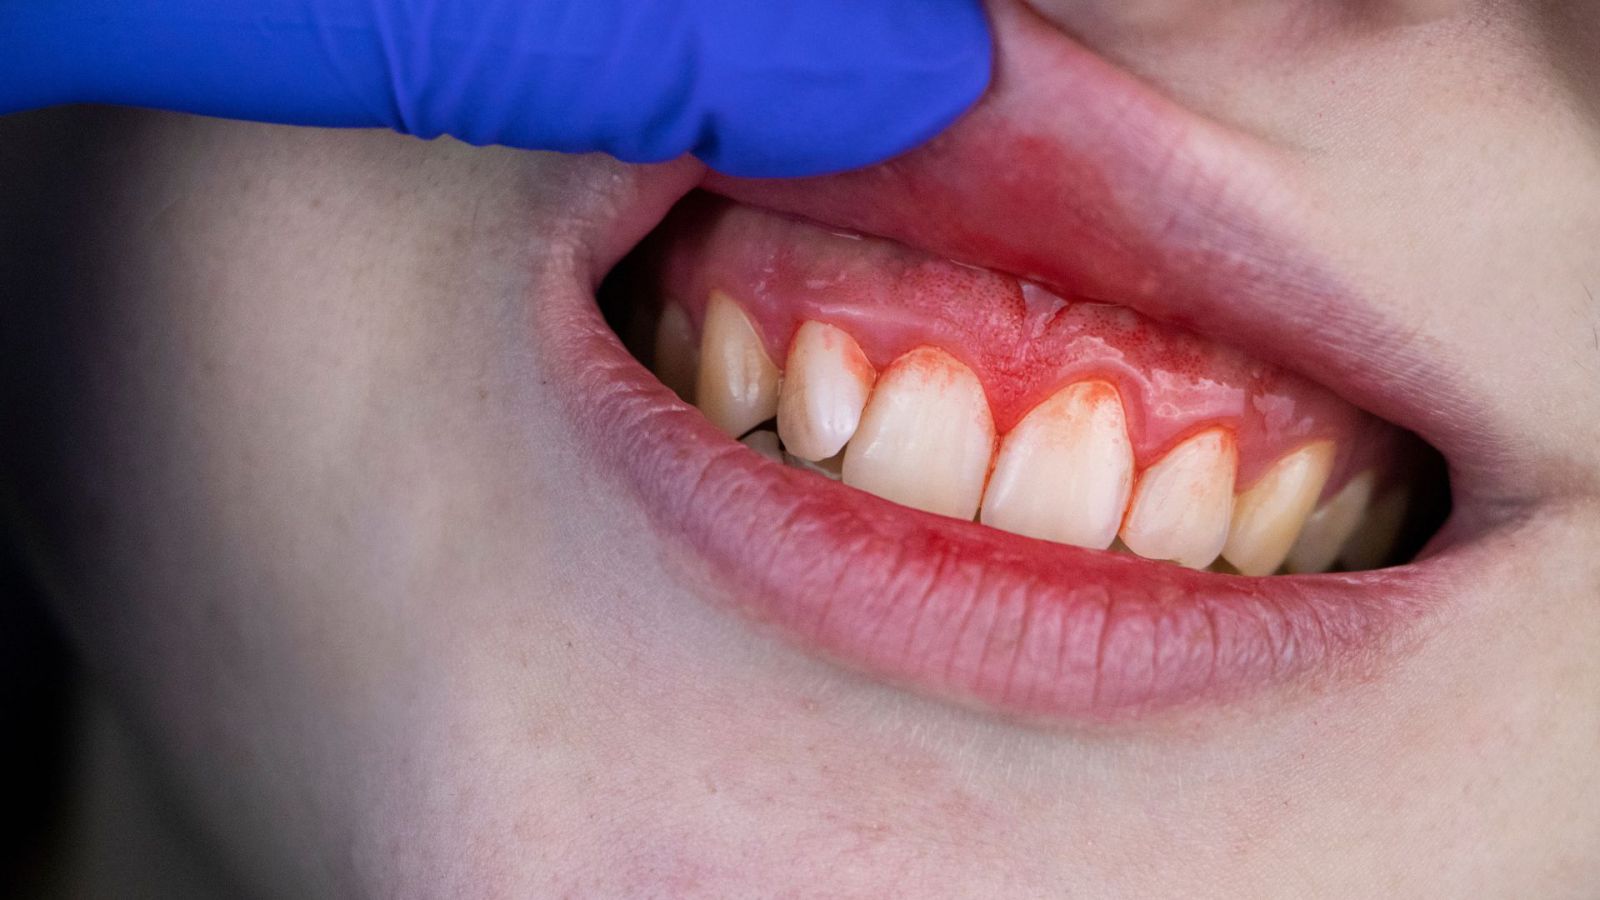

Có nên nhổ răng số 8 khi đang niềng răng?